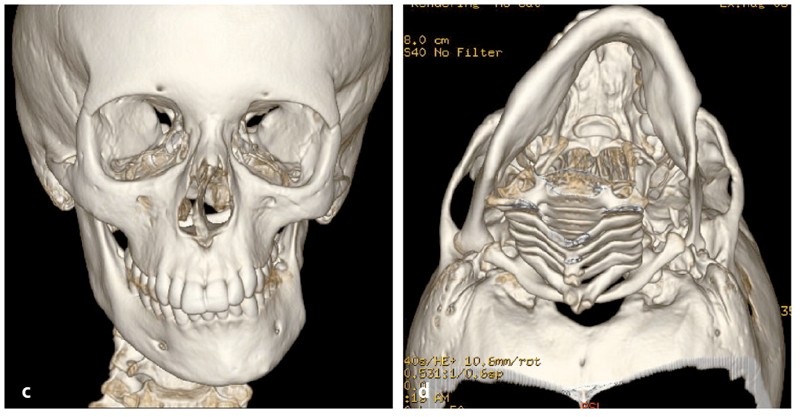

Analyse squelettique : les documents montrent une classe II squelettique modérée par rétrognathie mandibulaire dans un contexte de normodivergence. Les examens complémentaires confirment que la latérognathie mandibulaire gauche est la conséquence d’un hypo-développement des structures maxillaires et mandibulaires de ce même côté (fig. 2a, b et c). On observe sur les reconstructions 3D (à partir des coupes scanner) à l’aide du logiciel Osirix® : un corps mandibulaire fin, un ramus peu développé, un col du condyle grêle.